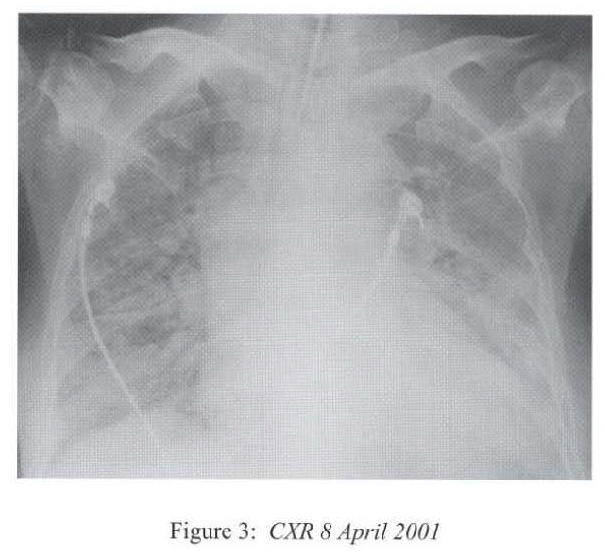

The respirology team was consulted at this time and we took over the case and managed her in the High Dependency Unit. The differential diagnoses included uncontrolled bacterial or fungal pneumonia, Pneumocystis carinii pneumonitis, viral pneumonitis, autoimmune pneumonitis, massive pulmonary embolism and massive pulmonary haemorrhage. She was treated with broad-spectrum antibiotics (piperacillin/tazobactam, amikacin) together with intravenous gancyclovir and cotrimoxazole. Supportive treatment included inotropes infusion, peritoneal dialysis, parenteral nutrition, and optimization of mechanical ventilation. Hydrocortisone was continued since she has been on systemic steroid for 3 months and the haemodynamic state was unstable. Bronchoscopy via the endotracheal tube showed copious mucoid secretions arising from both lung bases, and there was patchy mucosal excoriations involving the lower lobes. There was no sign of pulmonary haemorrhage. No transbronchial biopsy was attempted as she was on positive pressure ventilation and in critical state. CXR after bronchoscopy showed rapid resolution of pneumonia shadows in multiple areas (Figure 4).

Radiological features are also diverse and variable 15,16.On the chest radiograph, early signs include miliary shadows, diffuse reticular interstitial opacities, patchy alveolar opacities, segmental or lobar opacities. In the advanced stage, there can be extensive airspace shadows affecting both lungs, with occasional pleural or pericardial effusion. Without treatment, ARDS quickly evolves. Rarely, ARDS develops after antihelminthic treatment due to release of toxic breakdown products 17.On the abdominal radiograph, there can be thickened mucosal folds, segmental small bowel dilatation or perforation. Among all these variable radiological features, a characteristic pattern of Strongyloides hyperinfection has been described by the radiologists of Hong Kong, which consist of fleeting and rapidly changing CXR signs, predominant small bowel abnormality on AXR, and close temporal relationship of CXR & AXR signsl8. Detection of larvae in stool or other specimens is difficult (Table 1). Serological diagnosis19 is an attractive alternative but it is not available in Hong Kong.

Radiological features are also diverse and variable 15,16.On the chest radiograph, early signs include miliary shadows, diffuse reticular interstitial opacities, patchy alveolar opacities, segmental or lobar opacities. In the advanced stage, there can be extensive airspace shadows affecting both lungs, with occasional pleural or pericardial effusion. Without treatment, ARDS quickly evolves. Rarely, ARDS develops after antihelminthic treatment due to release of toxic breakdown products 17.On the abdominal radiograph, there can be thickened mucosal folds, segmental small bowel dilatation or perforation. Among all these variable radiological features, a characteristic pattern of Strongyloides hyperinfection has been described by the radiologists of Hong Kong, which consist of fleeting and rapidly changing CXR signs, predominant small bowel abnormality on AXR, and close temporal relationship of CXR & AXR signsl8. Detection of larvae in stool or other specimens is difficult (Table 1). Serological diagnosis19 is an attractive alternative but it is not available in Hong Kong.